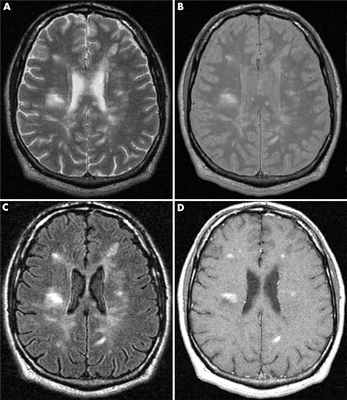

Как распознают рассеянный синдром на снимках? При рассеянном склерозе на снимках заметно характерно типичное распределение очагов в белом веществе головного мозга. Кроме того, для данного диагноза характерно поражение мозолистого тела, дугообразных волокон, височных долей, мозгового ствола, мозжечка и спинного мозга. Такое распределение очагов нехарактерно для иных патологических процессов, поэтому трудностей при постановке диагноза обычно не возникает. При ангиопатии возможны поражения ствола мозга, однако они обычно симметричны и располагаются центрально, в то время как очаги при рассеянном склерозе локализованы по периферии.

Чтобы МРТ показала все, даже самые мелкие очаги РС, ее нужно проводить по проколу МРТ головного мозга с контрастом на закрытом высокопольном МРТ аппарате мощностью не менее полутора Тесла. Контрастная МРТ головы покажет:

- визуализация контрастированных очагов разной формы ("узловое" и "кольцевидное" усиление), указывающих на различный возраст очагов демиелинизации в мозге.

Признаки рассеянного склероза на МРТ головного мозга манифестируют себя следующим образом:

- появлением новых очагов и увеличением старых;

- во время обострения проведение МРТ головы с контрастом будет приводить к тому, что очаги демиелинизации будут накапливать контраст причудливым кольцевым способом.

На изображениях, получаемых посредством МРТ при рассеянном склерозе, диагност четко видит:

- более интенсивный сигнал, что на картинке выражено наличием очага или очагов

- общее количество очагов

- расположение очагов и их близость к важным структурам головного мозга.

МРТ критериями обострения PC служат следующие признаки:

- образование новых и повторное появление исчезнувших очагов;

- увеличение в размерах уже существующих очагов.